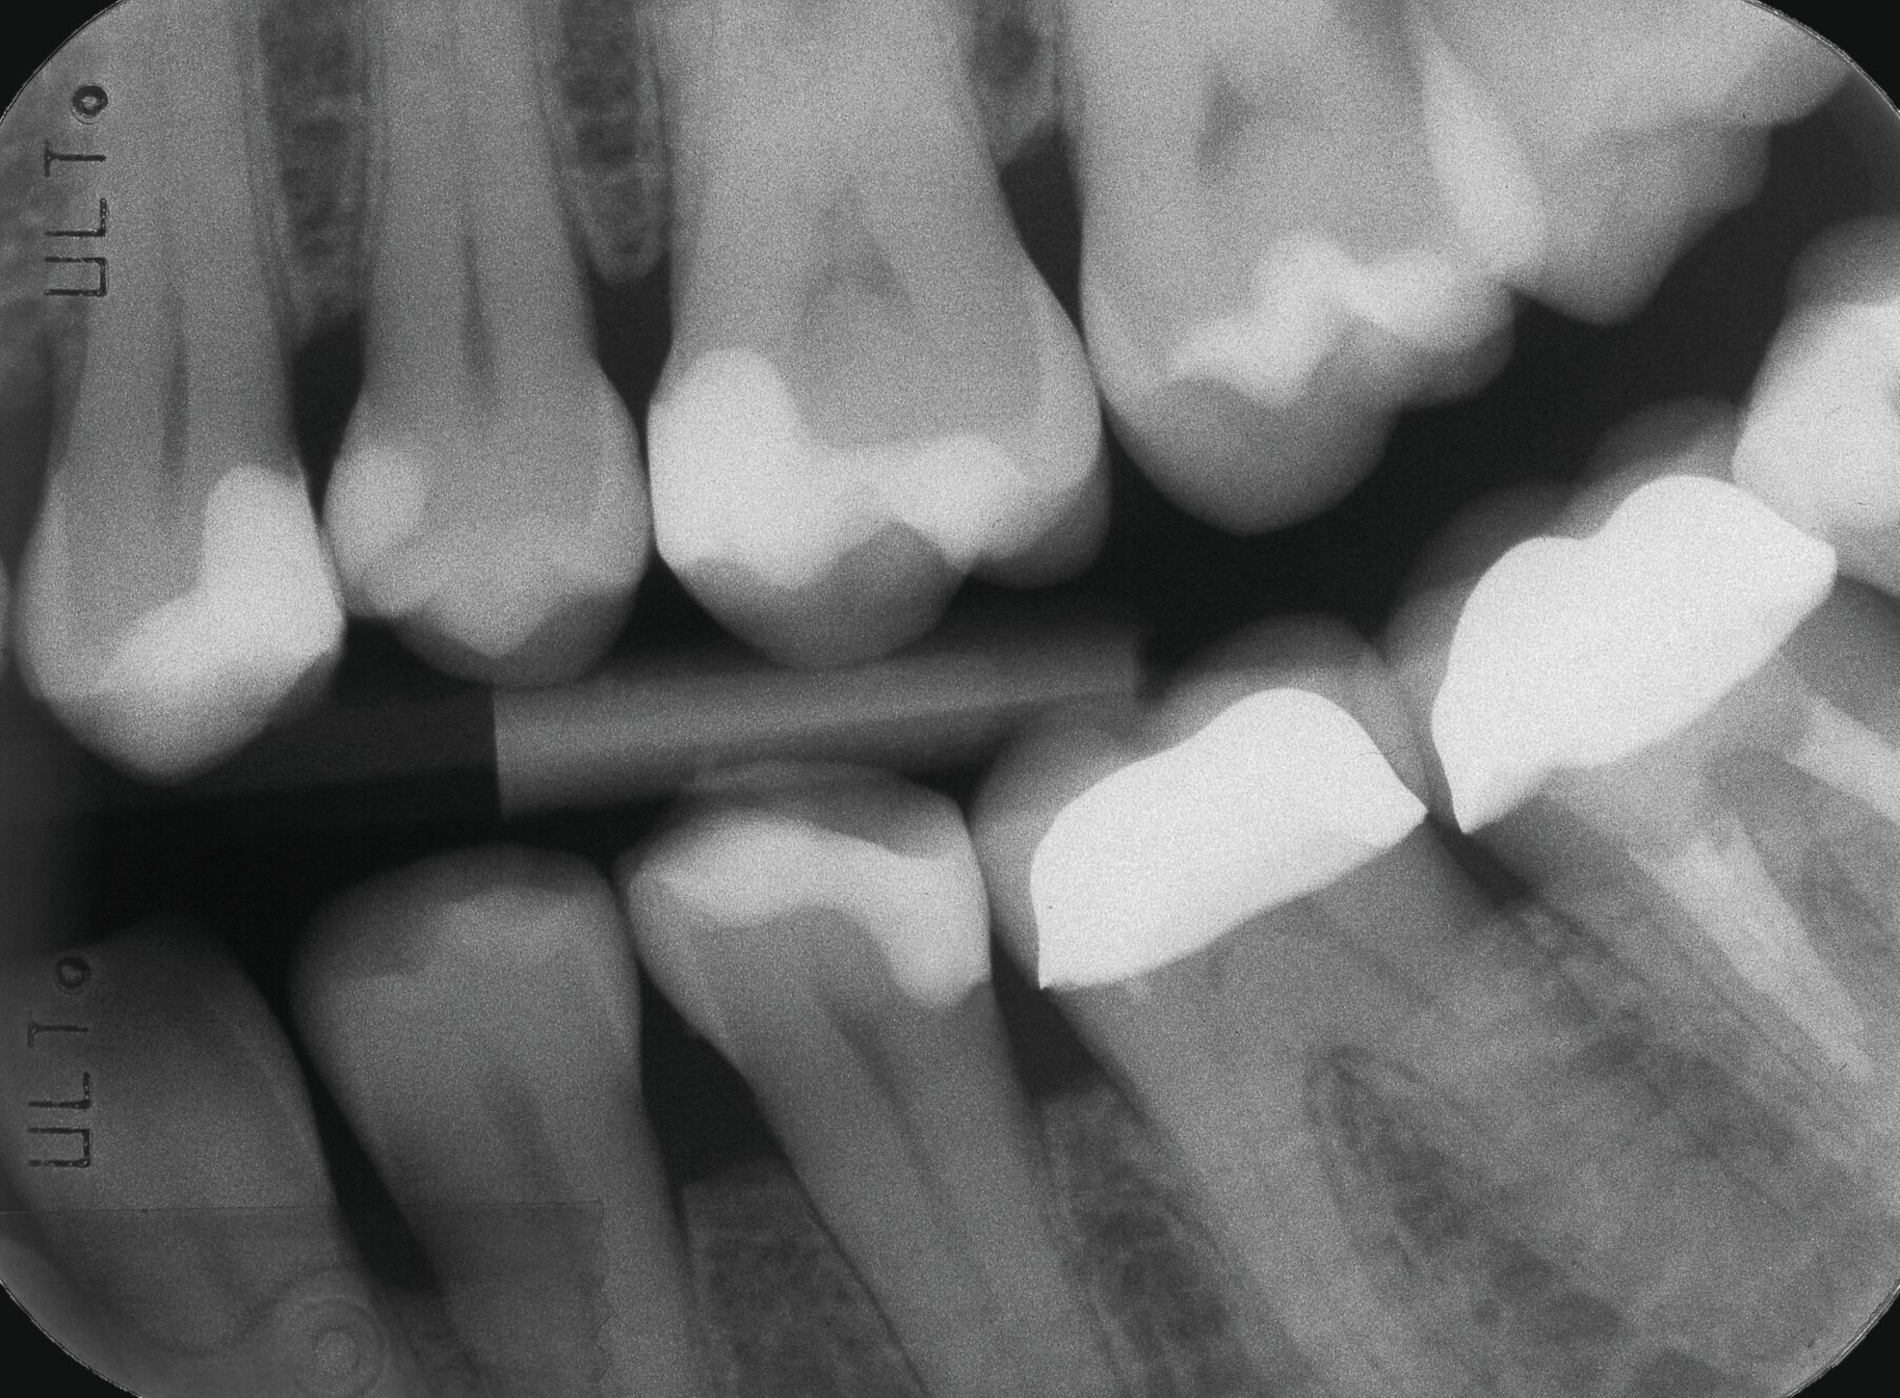

Darüber hinaus muss man bei der Erörterung konventioneller Zementunterfüllungen realistischerweise immer in Betracht ziehen, dass niemals jedes einzelne Dentinkanälchen von Zement bedeckt sein wird und somit selbstverständlich immer zusätzlich mit einem Adhäsivsystem (für Schmelz und Dentin) gearbeitet werden muss. Dies gilt vor allem für die Approximalbereiche, in denen der Abstand zur Pulpa oft geringer ist als okklusal (Abbildung 1).

Eine besondere Situation stellt die Caries profunda dar. Hier gibt es hinreichend Evidenz, dass unterhalb einer Restdentindicke von 300 μm zum einen die Gefahr besteht, dass kurzkettige Monomere das Dentin durchdringen und Biomineralisationsprozesse der Odontoblasten stören können [Galler et al., 2011; Schmalz et al., 2001]. Praktisch viel wichtiger ist jedoch ein rein geometrisches Problem: Bondet man eine Kompositrestauration im Dentin so nahe an der Pulpa, bilden sich neben der für die Dentinhaftung verantwortlichen Hybridschicht auch Harzzotten (Resin Tags), die bis zu 300 μm in das Dentin eindringen (Abbildung 2). Das würde bedeuten, dass sich die Tags praktisch am Eingang der Pulpa befinden, was weder klinisch noch anatomisch sinnvoll erscheint. Gleiches gilt für pulpanahe Bereiche bei Kronenfrakturen. Insbesondere bei Kindern sind die Dentintubuli noch weit offen und das Dentin ist an diesen Stellen hoch permeabel [Krastl et al., 2021].

Für solche tiefen Areale existieren zwei unterschiedliche Lösungsansätze: Entweder man exkaviert einfach weniger aggressiv [Schwendicke et al., 2013] oder man appliziert ausschließlich in diesen Bereichen kleine Mengen klassischer „Cp-Medikamente“ oder Kalziumsilikatzemente [Schmidt et al., 2020] im Sinne einer kleinen Unterfüllung zur Blockade der „Tags“ [European Society of Endodontology, 2019]. Der weniger tief exkavierte Rest der Kavität wird aber auch hier vollständig mit einem Adhäsivsystem versiegelt und nicht mit einer konventionellen Zementunterfüllung [Arandi et al., 2020; European Society of Endodontology, 2019]. Eine korrekte Indikationsstellung für die Applikation eines Cp-Materials ist jedoch wichtig, da diese Materialien die Gesamthaftung in der restlichen Kavität reduzieren können [Frankenberger et al., 2021]. Die adhäsive Dentinversiegelung stellt heute den wirksamsten Schutz des Pulpa-Dentin-Komplexes dar (Abbildungen 3 und 4) [Arandi et al., 2020]. Das Risiko, dass die Pulpa dadurch einen irreversiblen Schaden erleidet, ist äußerst gering und minimal im Vergleich zum Schädigungspotenzial eines Diamantschleifers, der bei Amalgam und Gold oftmals „im Gesunden“ statt rein minimalinvasiv verwendet werden musste [Olmez et al., 1995; Schweikl et al., 2017].